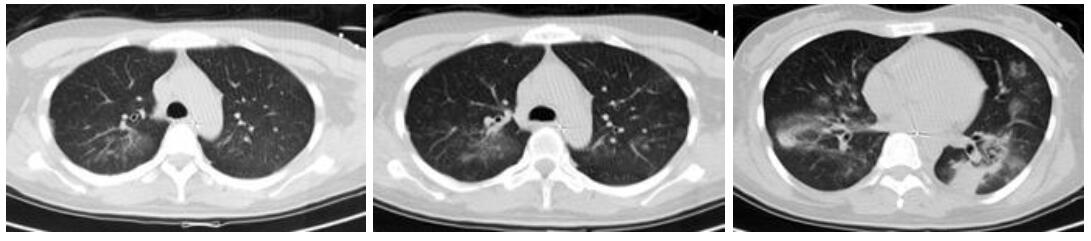

病例2,女,55岁,有鸽子喂养史,近半个月来咳嗽发热,咳剧时伴胸闷气喘,活动后加重,近1周出现纳差,伴呕吐、腹泻。入院查体:体温38 ℃,脉搏126次/min,呼吸32次/min,血压91/48 mmHg。神清,无皮疹,浅表淋巴结无肿大,右肺闻及湿啰音,心律齐,未闻及杂音,肝脾肋下未触及。胸部CT示右肺大片实变,见图 3A。甲、乙型流感抗原检测阴性。入院诊断:重症社区获得性肺炎。予无创机械通气,美罗培南+莫西沙星抗感染,奥司他韦抗病毒,入院第3天查胸片示两肺斑片状模糊影(图 3B),予气管插管辅助通气,查PCT 7.88 ng/mL。改用阿奇霉素+万古霉素抗感染。入院第8天行肺泡灌洗液mNGS检测:鹦鹉热衣原体(序列数314),鲍曼不动杆菌(序列数23),改舒普深+替加环素治疗。经治疗后,患者症状无明显好转,并发严重上消化道出血,入院第13天查胸片示病灶范围扩大(见图 3C),因病情危重,生命体征不平稳未行CT复查,患者病情进行性恶化,治疗14 d后死亡。

| A:入院时胸部CT,右肺大片实变;B:入院第3天床边胸片,两肺斑片状模糊影;C:入院第13天床边胸片,两肺斑片状模糊影,较前有进展 图 3 病例2胸部检查结果 |